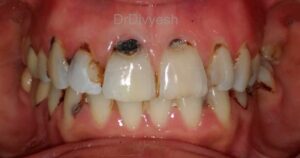

દાંતની કોઈ સપાટીએ દાંતનું ખનીજ બંધારણ ઓગળી જતા પડેલા ખાડાને દાંતનો સડો કહેવાય. સફેદ કલરના દાંતમાં દાંતનો સડો કાળા કે બ્રાઉન કલરના ખાડા રૂપે દેખાય છે. શરૂઆતના તબક્કામાં દાંતનો સડો માત્ર ટપકા કે પાતળી લાઈન જેટલો હોય છે.

બે દાંતની વચ્ચેની સપાટીએથી જો સડો હોય તો એવું પણ બને કે સડો દેખાય જ નહિ, અને તેવા સડાની તપાસ માત્ર એક્ષ-રે દ્વારા જ કરી શકાય છે.

દાંતના સડાના શરૂઆતના તબક્કામાં કોઈ પણ જાતનો દુખાવો થતો નથી. ચિત્રમાં બતાવ્યા પ્રમાણે જયારે દાંતનો સડો ઇનેમલ અને ડેન્ટીનને ખોતરી પલ્પ સુધી પહોચે ત્યારે જ દુખાવો થાય છે જે ઘણી વખત અસહ્ય અથવા કયારેક આશ્ચર્યજનક રીતે બિલકુલ થતો નથી.